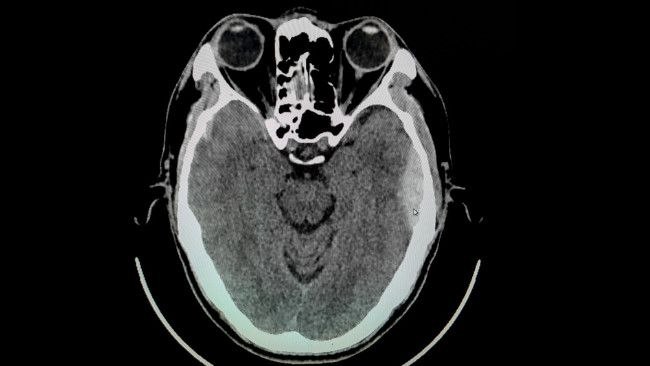

- Pemeriksaan computerized tomography (CT) scan yang dapat menunjukkan adanya massa padat yang mendesak struktur otak menjauh dari tulang tengkorak.